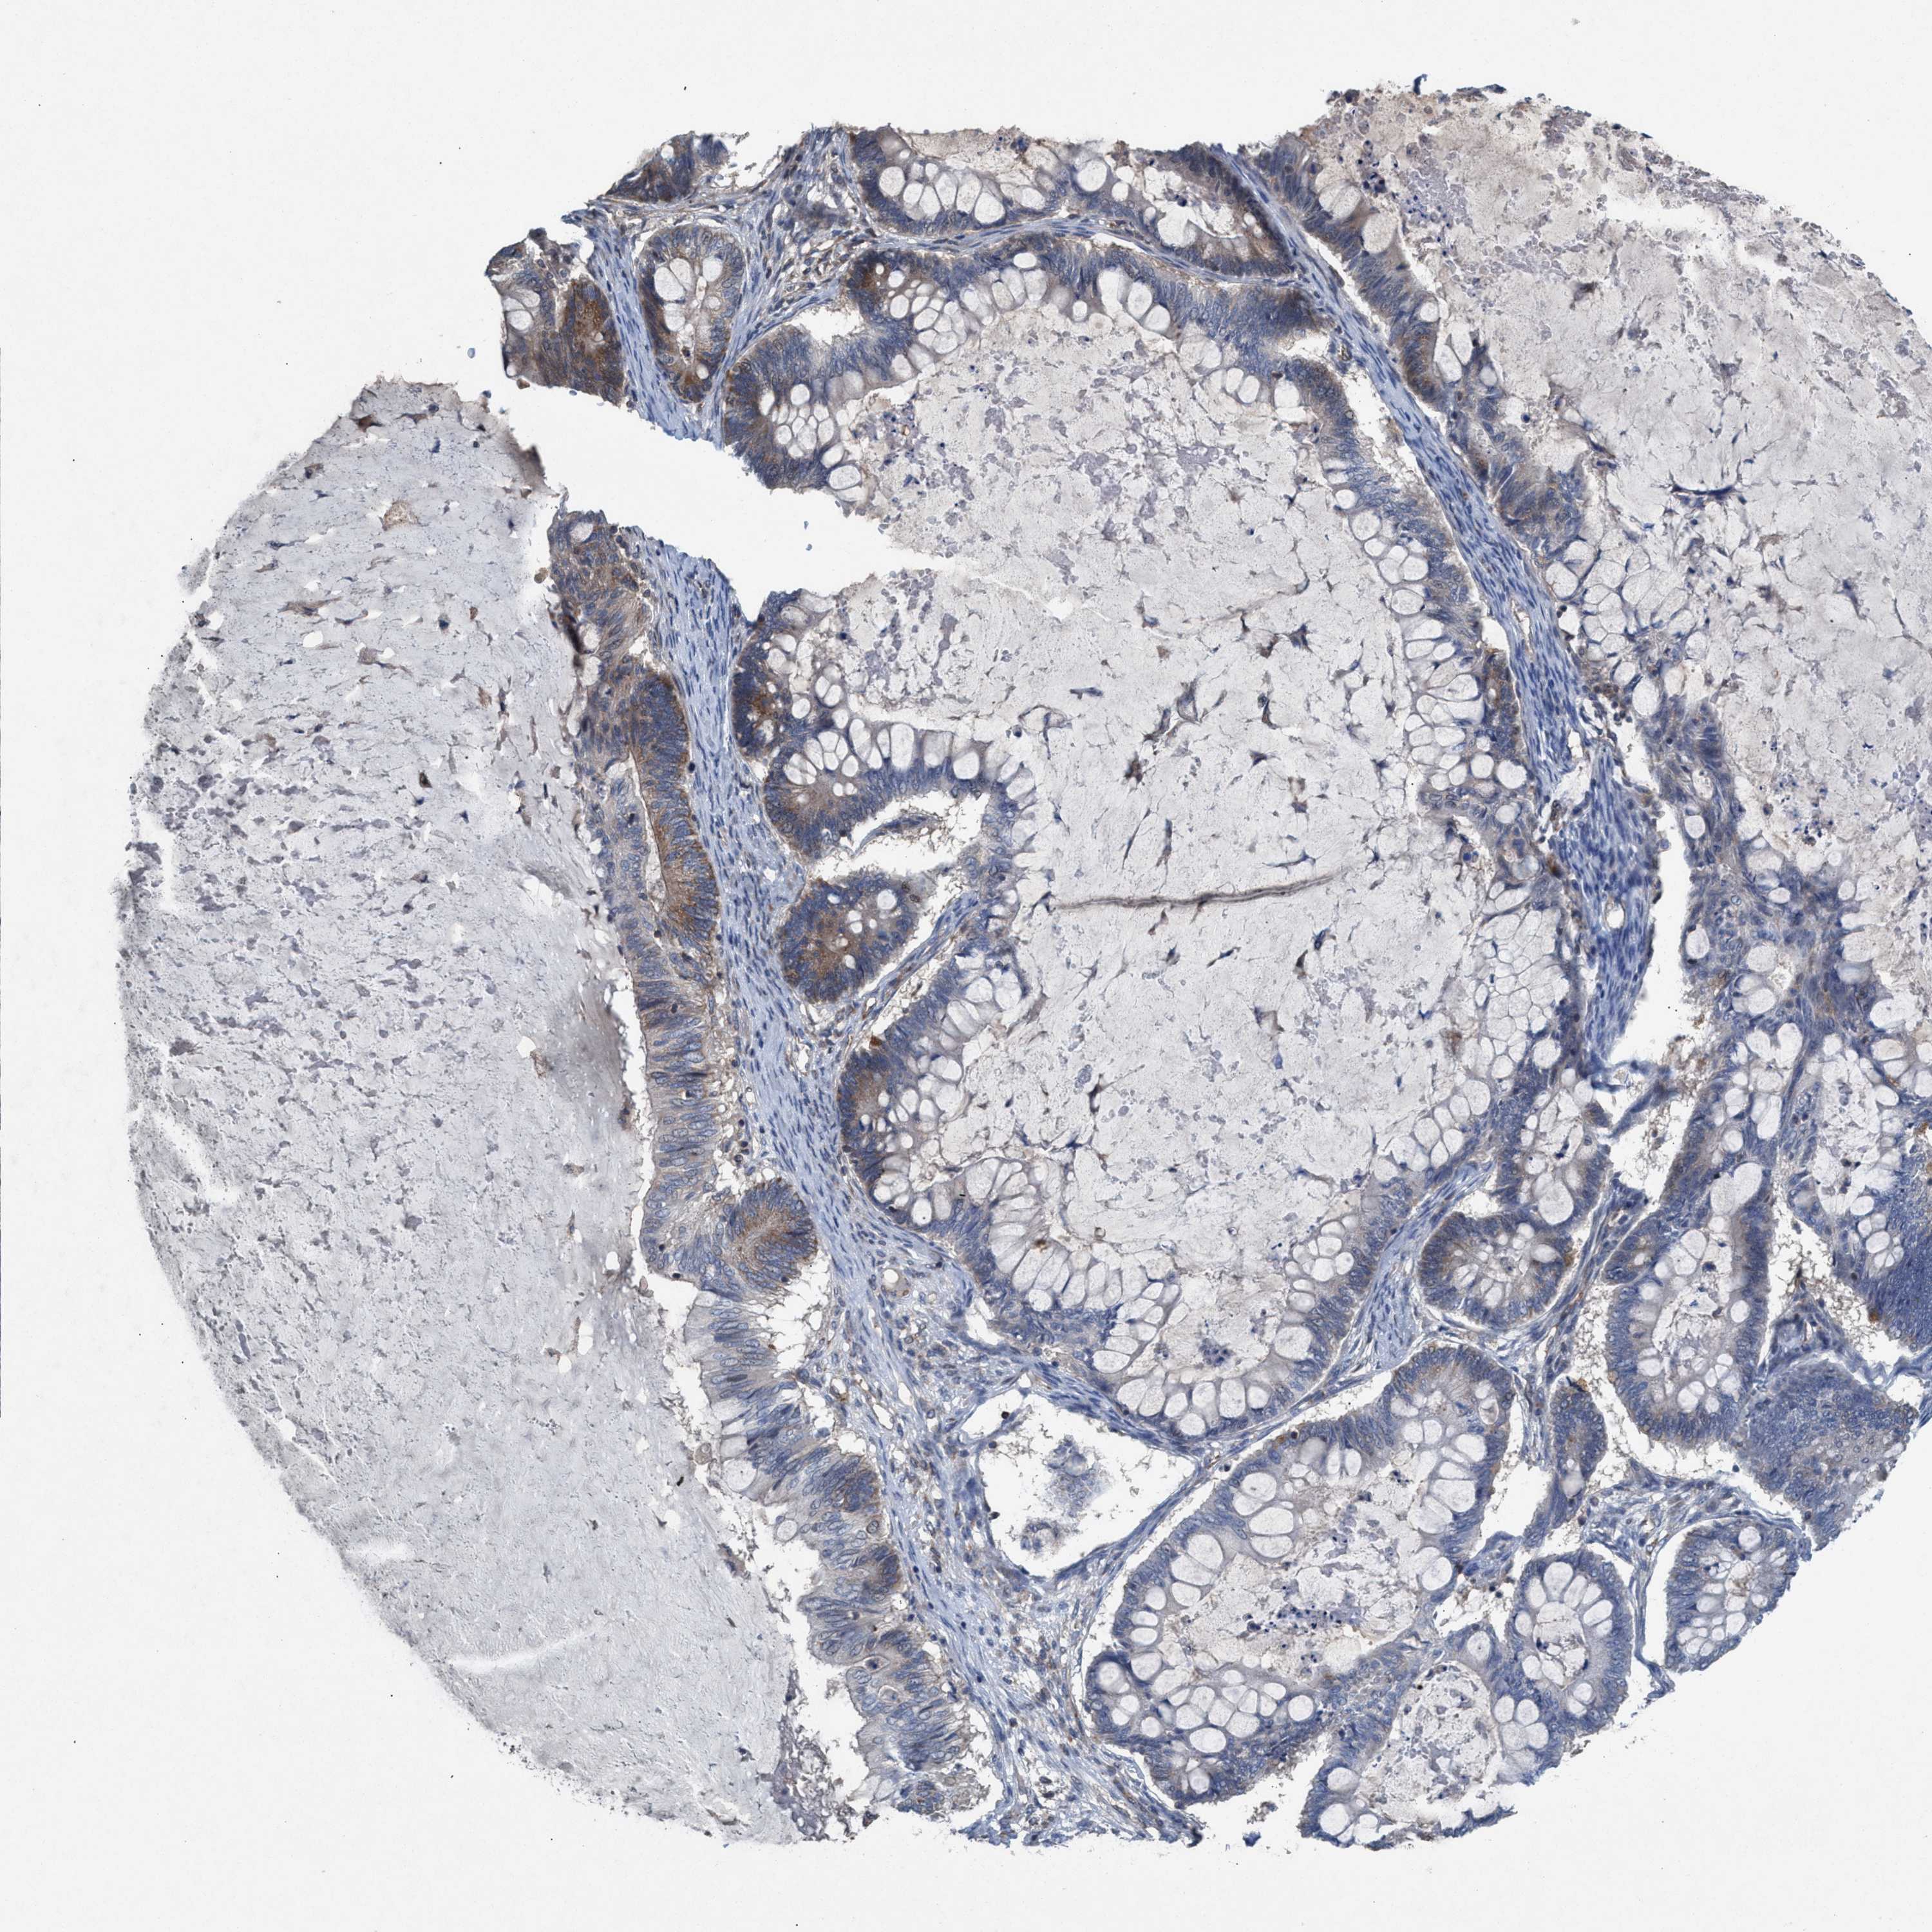

OVARIAN CANCER - Protein expressioni

A mouse-over function shows sample information and annotation data. Click on an image to view it in a full screen mode. Samples can be filtered based on level of antibody staining by selecting one or several of the following categories: high, medium, low and not detected. The assay and annotation is described here.

Note that samples used for immunohistochemistry by the Human Protein Atlas do not correspond to samples in the TCGA dataset.

Antibody stainingi

Antibody staining in the annotated cell types in the current human tissue is reported as not detected, low, medium, or high, based on conventional immunohistochemistry profiling in selected tissues. This score is based on the combination of the staining intensity and fraction of stained cells.

Each image is clickable and will lead to virtual microscopy that enables deeper exploration of all samples and also displays staining intensity scores, fraction scores and subcellular localization as well as patient and tissue information for each sample.

Antibody HPA021598

Staining

High

Medium

Low

Not detected

Intensity

Strong

Moderate

Weak

Negative

Quantity

>75%

75%-25%

<25%

None

Location

Nuclear

Cytoplasmic/membranous

Cytoplasmic/membranous,nuclear

Cystadenocarcinoma, serous, NOS

Carcinoma, endometroid

Cystadenocarcinoma, mucinous, NOS